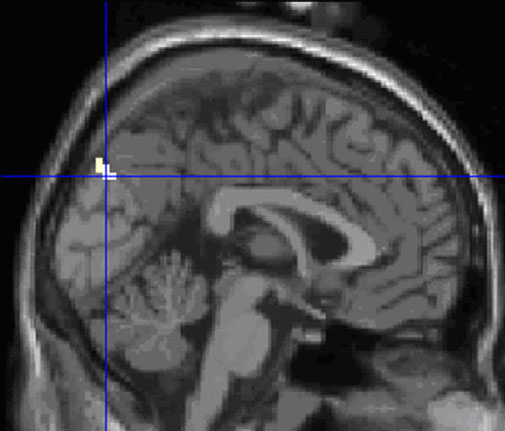

In the homosexual group, the F–F stimulus identified great activity in a large number of brain regions, including the left superior frontal gyrus, right and left medial frontal gyrus, left and right cerebellum, left middle occipital gyrus (BA 19), right lingual gyrus (BA 18), left precuneus, right middle temporal gyrus, left superior temporal gyrus (BA 38), left thalamus, and left supplementary motor area.In the heterosexual group, M–M stimuli elicited great activations in the left middle frontal gyrus, right middle frontal gyrus (BA 6), left inferior frontal gyrus (BA 45), right inferior frontal gyrus (BA 47), left middle temporal gyrus, right middle temporal gyrus (BA 37, BA 39), left superior temporal gyrus (BA 13), right superior temporal gyrus (BA 38), left inferior occipital gyrus (BA 18), bilateral caudate, bilateral thalamus, bilateral insula, left putamen, right parahippocampal gyrus, right cerebellum, right anterior cingulate (BA 42), and right amygdala.OK, so that's a bunch of areas that are activated relative to doing nothing (instead of relative to watching a neutral film). I won't try to interpret those results. How about comparing the Disgust vs. Rest responses of the gay and straight men? There was one region of the brain more active in each of the groups: left ventromedial prefrontal cortex for gay men (Fig. 4), and left cuneus [visual cortex] for straight men (Fig. 5).

Fig. 4 (modified from Zhang et al., 2010). Aversive sexual stimuli compared to rest: stronger brain activation in homosexual men compared to heterosexual men in the left medial frontal gyrus (maximum at −1, 39, −12).

Fig. 5 (modified from Zhang et al., 2010). Aversive sexual stimuli compared to rest: stronger brain activation in heterosexual men compared to homosexual men in the left cuneus (maximum at −1, −81, 36). [two-sample t-test, p less than 0.001 uncorrected, extend 5 voxels]Why?? What does it mean?